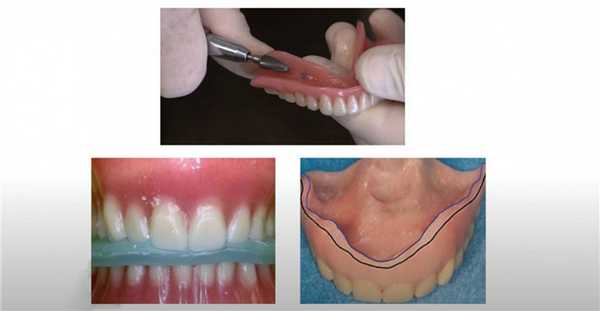

Перебазировка съемного протеза

А вы знаете, что делать, если съемный протез начал расшатываться? Многие пациенты пренебрегают регулярной перебазировкой. Вместо этого, они пытаются зафиксировать искусственную челюсть на большее количество клея или засунуть протез подальше в рот. В этой статье расскажем, почему это было бы ошибкой. Мы собрали самую важную информацию о перебазировании зубных протезов (обязательной и плановой).

При адентии альвеолярный отросток опускается из-за отсутствия стимуляции от зубов. Нарушается плотность посадки, возникают проблемы с жеванием. Немедленно обратитесь к стоматологу, если съемная челюсть расшаталась.

Что это такое?

Перебазирование съемного зубного протеза - это стоматологическая технология восстановления поверхности, которая соприкасается с деснами, чтобы он фиксировался плотно. Заключается в добавлении нового полимерного материала на установочную поверхность для заполнения пространства между контуром каркаса и измененным альвеолярным гребнем.

Врач работает только с базисом, не затрагивает остальные части конструкции. Перебазировка предотвращает избыточное давление протеза на мягкие ткани десны. Результат процедуры - стабилизация съемной челюсти, восстановление прикуса, пропадает дискомфорт во время еды.

Мы предупреждаем всех пациентов со съемными протезами, что периодически необходимо оценивать и исправлять прилегание базиса к десневому гребню. Это рутинная процедура, ее нужно делать регулярно раз в 6 месяцев на контрольном осмотре. Если регулярно не перебазировать, вы рискуете получить повреждение или раздражение слизистой. Обслуживание ортопедической конструкции продлит срок службы, исключит поломки, способствует правильному распределению жевательной нагрузки на челюсть